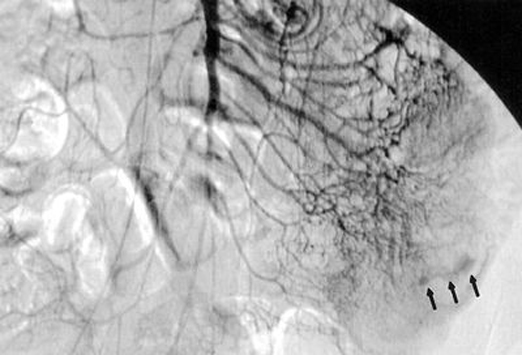

Dizziness test a real (V)HIT The hospital is the first in the region to offer the Video Head Impulse Test, a quick and painless way to identify the causes of debilitating dizziness. It offers a new view into the labyrinthine workings of the inner ear. "We can tell exactly what your ear is doing. Before it was a black box," says UCH otoneurologist Carol Foster, MD. >>More